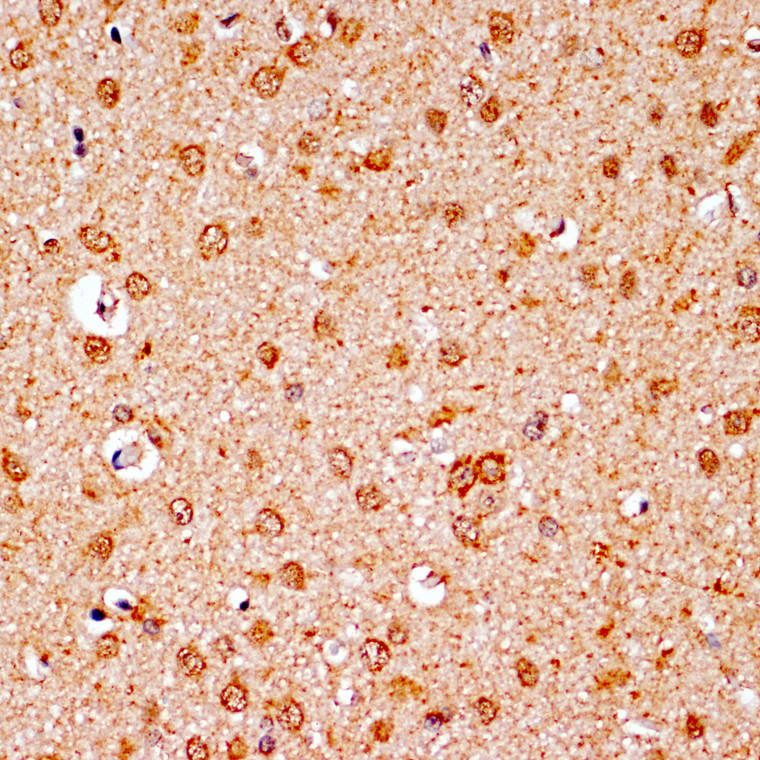

Rabbit polyclonal antibody anti-Bcl-2 (1-239) is suitable for use in Western Blot research applications. |

BCL2 |

Recombinant fusion protein containing a sequence corresponding to amino acids 1-239 of human Bcl-2 (NP_000624.2). |

MAHAGRTGYDNREIVMKYIH YKLSQRGYEWDAGDVGAAPP GAAPAPGIFSSQPGHTPHPA ASRDPVARTSPLQTPAAPGA AAGPALSPVPPVVHLTLRQA GDDFSRRYRRDFAEMSSQLH LTPFTARGRFATVVEELFRD GVNWGRIVAFFEFGGVMCVE SVNREMSPLVDNIALWMTEY LNRHLHTWIQDNGGWDAFVE LYGPSMRPLFDFSWLSLKTL LSLALVGACITLGAYLGHK |

| Function | Suppresses apoptosis in a variety of cell systems including factor-dependent lymphohematopoietic and neural cells. Regulates cell death by controlling the mitochondrial membrane permeability. Appears to function in a feedback loop system with caspases. Inhibits caspase activity either by preventing the release of cytochrome c from the mitochondria and/or by binding to the apoptosis-activating factor (APAF-1). Also acts as an inhibitor of autophagy: interacts with BECN1 and AMBRA1 during non-starvation conditions and inhibits their autophagy function. May attenuate inflammation by impairing NLRP1-inflammasome activation, hence CASP1 activation and IL1B release. |

| Cellular Localisation | Mitochondrion Outer MembraneSingle-Pass Membrane ProteinNucleus MembraneEndoplasmic Reticulum MembraneCytoplasm |